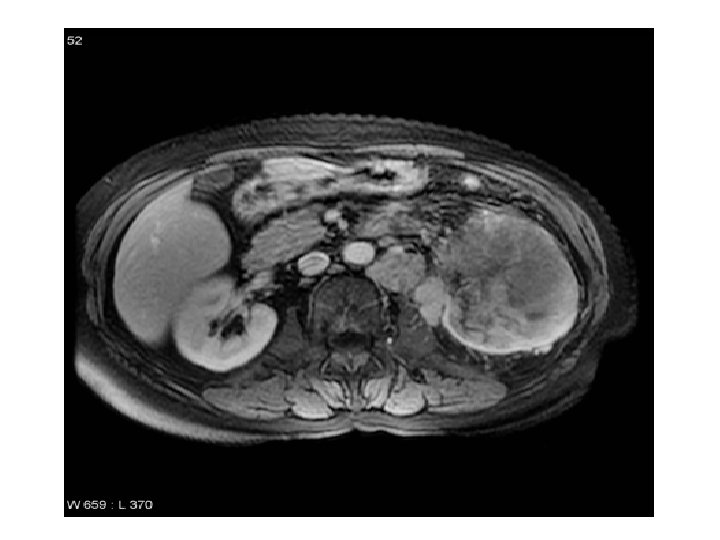

Case (3) • Elderly male patient with recurrent urinary tract infections.